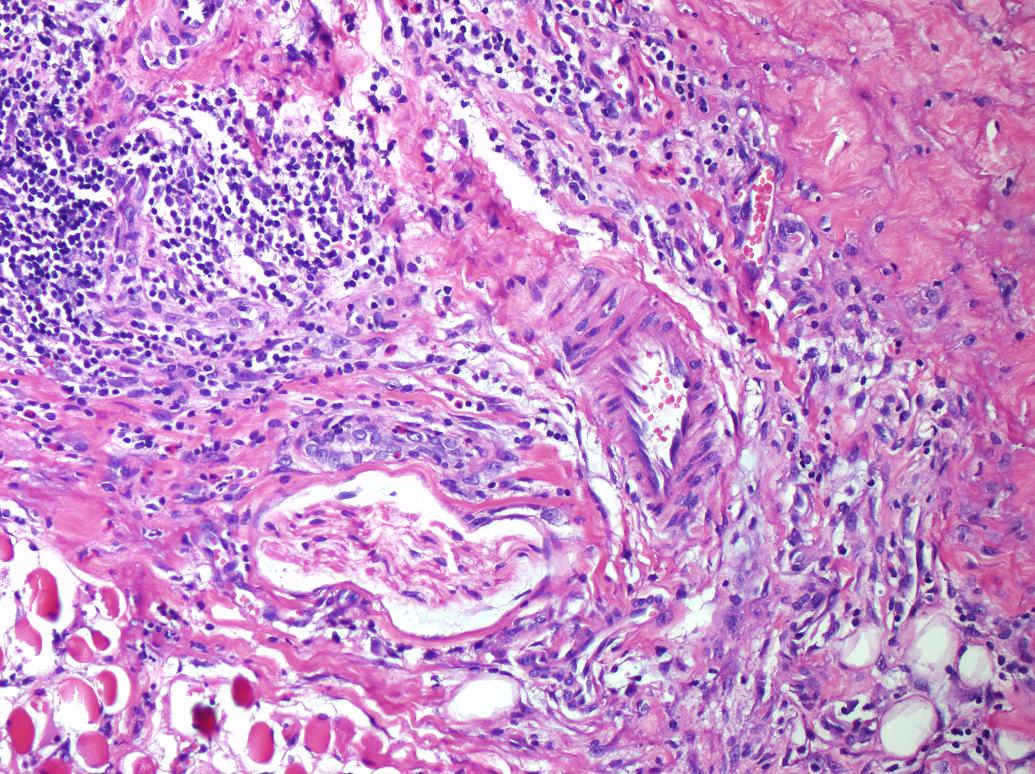

Cervical Lymphadenitis Due to Nodular Fasciitis in a Child

Nodular fasciitis is a benign, reactive proliferation of fibroblasts in the subcutaneous tissues. It usually affects the trunk and upper extremities, and rarely the head and neck region of young adults. It is rare among children and the histologic findings may incorrectly suggest malignant lesions. We describe a two-year-old girl that referred to our clinic with complaints of fever and swelling on the right side of neck and diagnosed as lymphadenitis clinically. Cervical lymphadenitis due to nodular fasciitis is a rarity. We emphasize that nodular fasciitis needs to be included in the differential diagnoses of neck lymphadenitis during childhood.